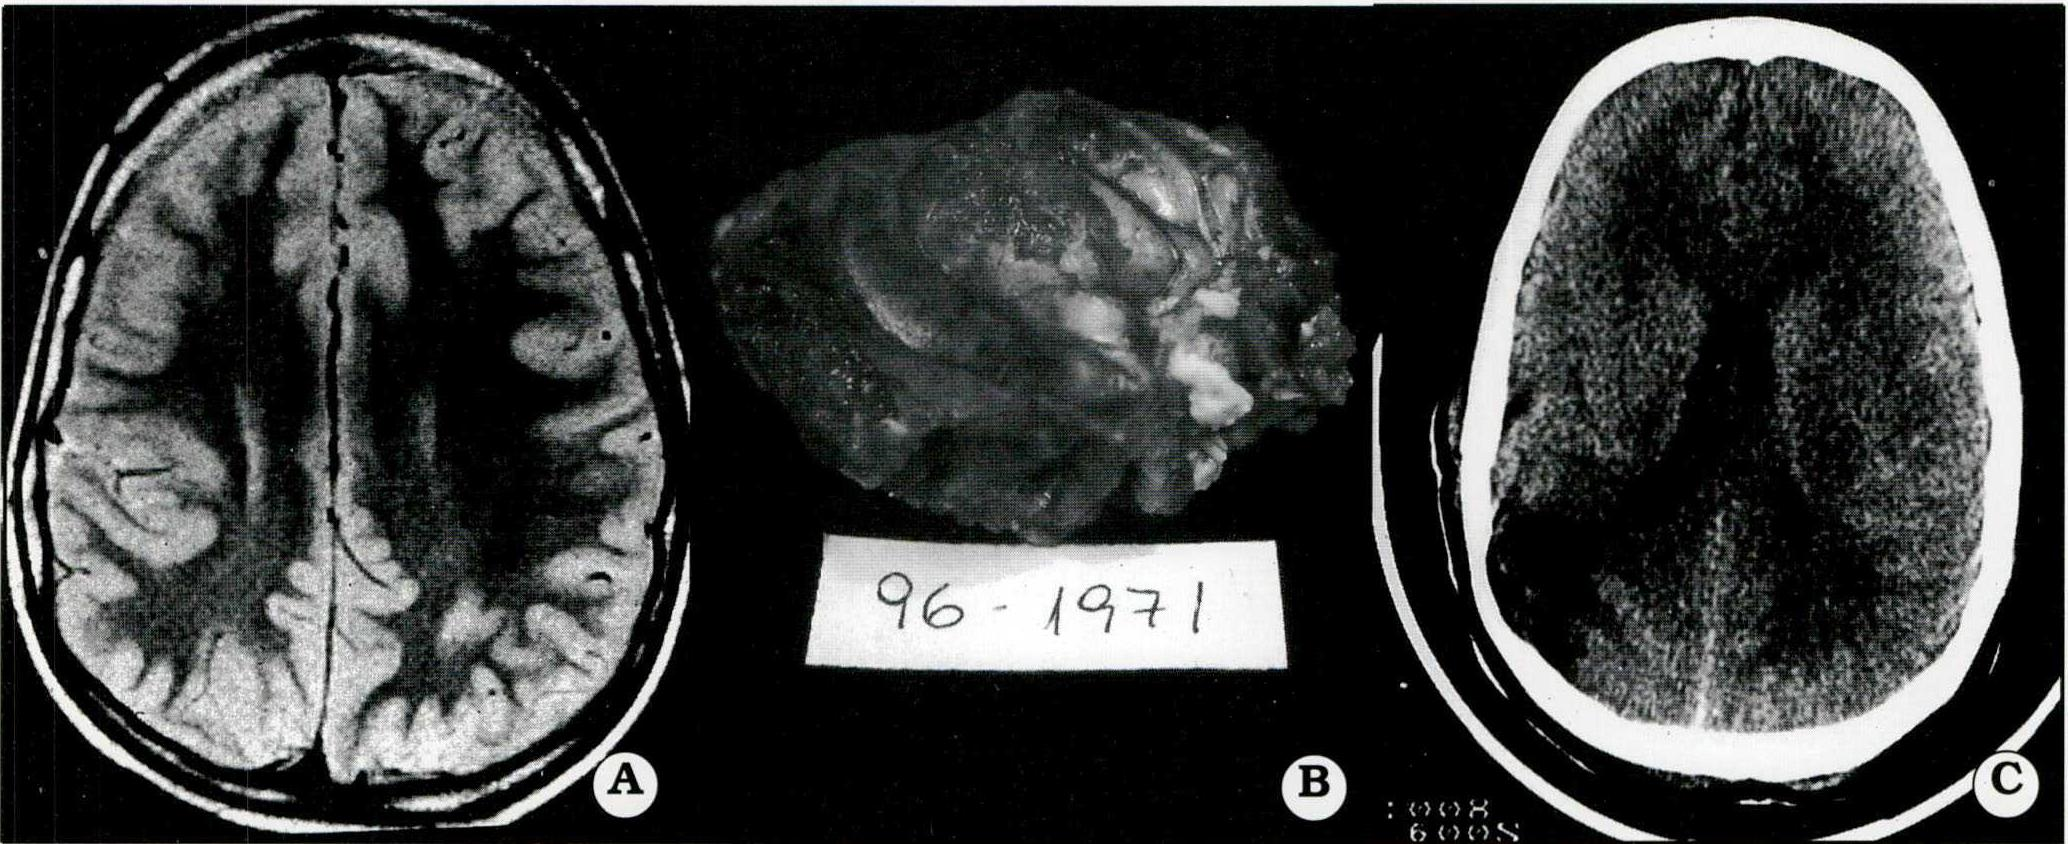

Es importante remarcar el aporte que significó el advenimiento de las nuevas técnicas electroencefalográficas en la selección del candidato a cirugía. Hacia fines de 1995 y comienzo del '96 se inauguraron en el país las primeras unidades de Video-telemetría, lo que mejoró y enriqueció el estudio de los candidatos. Esto permitió llegar a la cirugía con información suficiente para reducir el porcentaje de decisiones intraoperatorias, que dependían de la ECoG, con un potencial margen de error derivado del factor anestésico. La videotelemetría se efectuó en 47/68 (69,1%) de los pacientes. Los 21 pacientes operados sin Video-telemetría prequirúrgica tenían lesiones extensas con buen correlato con la clínica y el EEG prolongado computarizado (Fig. 1).

Fig. 1. Paciente varón de 9 años de edad, con crisis convulsivas mensuales. Los cortes axiales y coronales pre y postoperatorios de la IRM muestran un cavernoma del área central y su resección. Cuatro años de evolución postoperatoria sin crisis y sin secuelas

Fig. 5A. IRM, displasia del área parieto-central derecha (paciente varón, 10 años, con 6 años de evolución de epilepsia y hemiparesia congénita). Bajo guía ECoG se efectuó una lesionectomía ampliarla No se resecó la parte de la lesión superpuesta al área sensorial primaria del cerebro. Actualmente se encuentra en clase ID de Engel. B. La pieza resecada. C. TAC de control postoperatorio inmediato